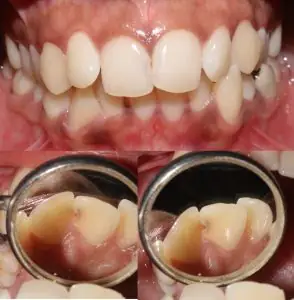

Restoring Class 3 caries along the midline in rotated teeth